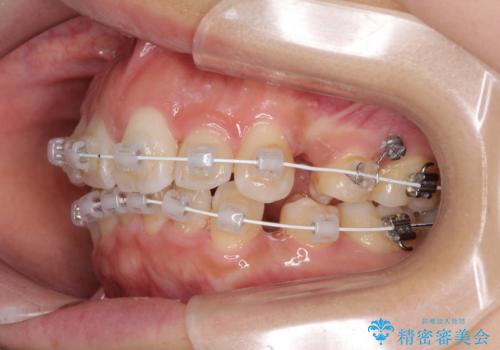

- 審美装置

- 2年5ヶ月

- 10-30回

- 上下の出っ歯を気にして来院された患者様です。

口元を積極的に引っ込めるために、上下左右の第一小臼歯を4本抜歯することとしました。

下顎の正中を上顎に合わせる処置が難航し、期間が長引きました。

最終的には上下の正中も合い、横顔の印象が変わるほどスッキリとした口元となりました。